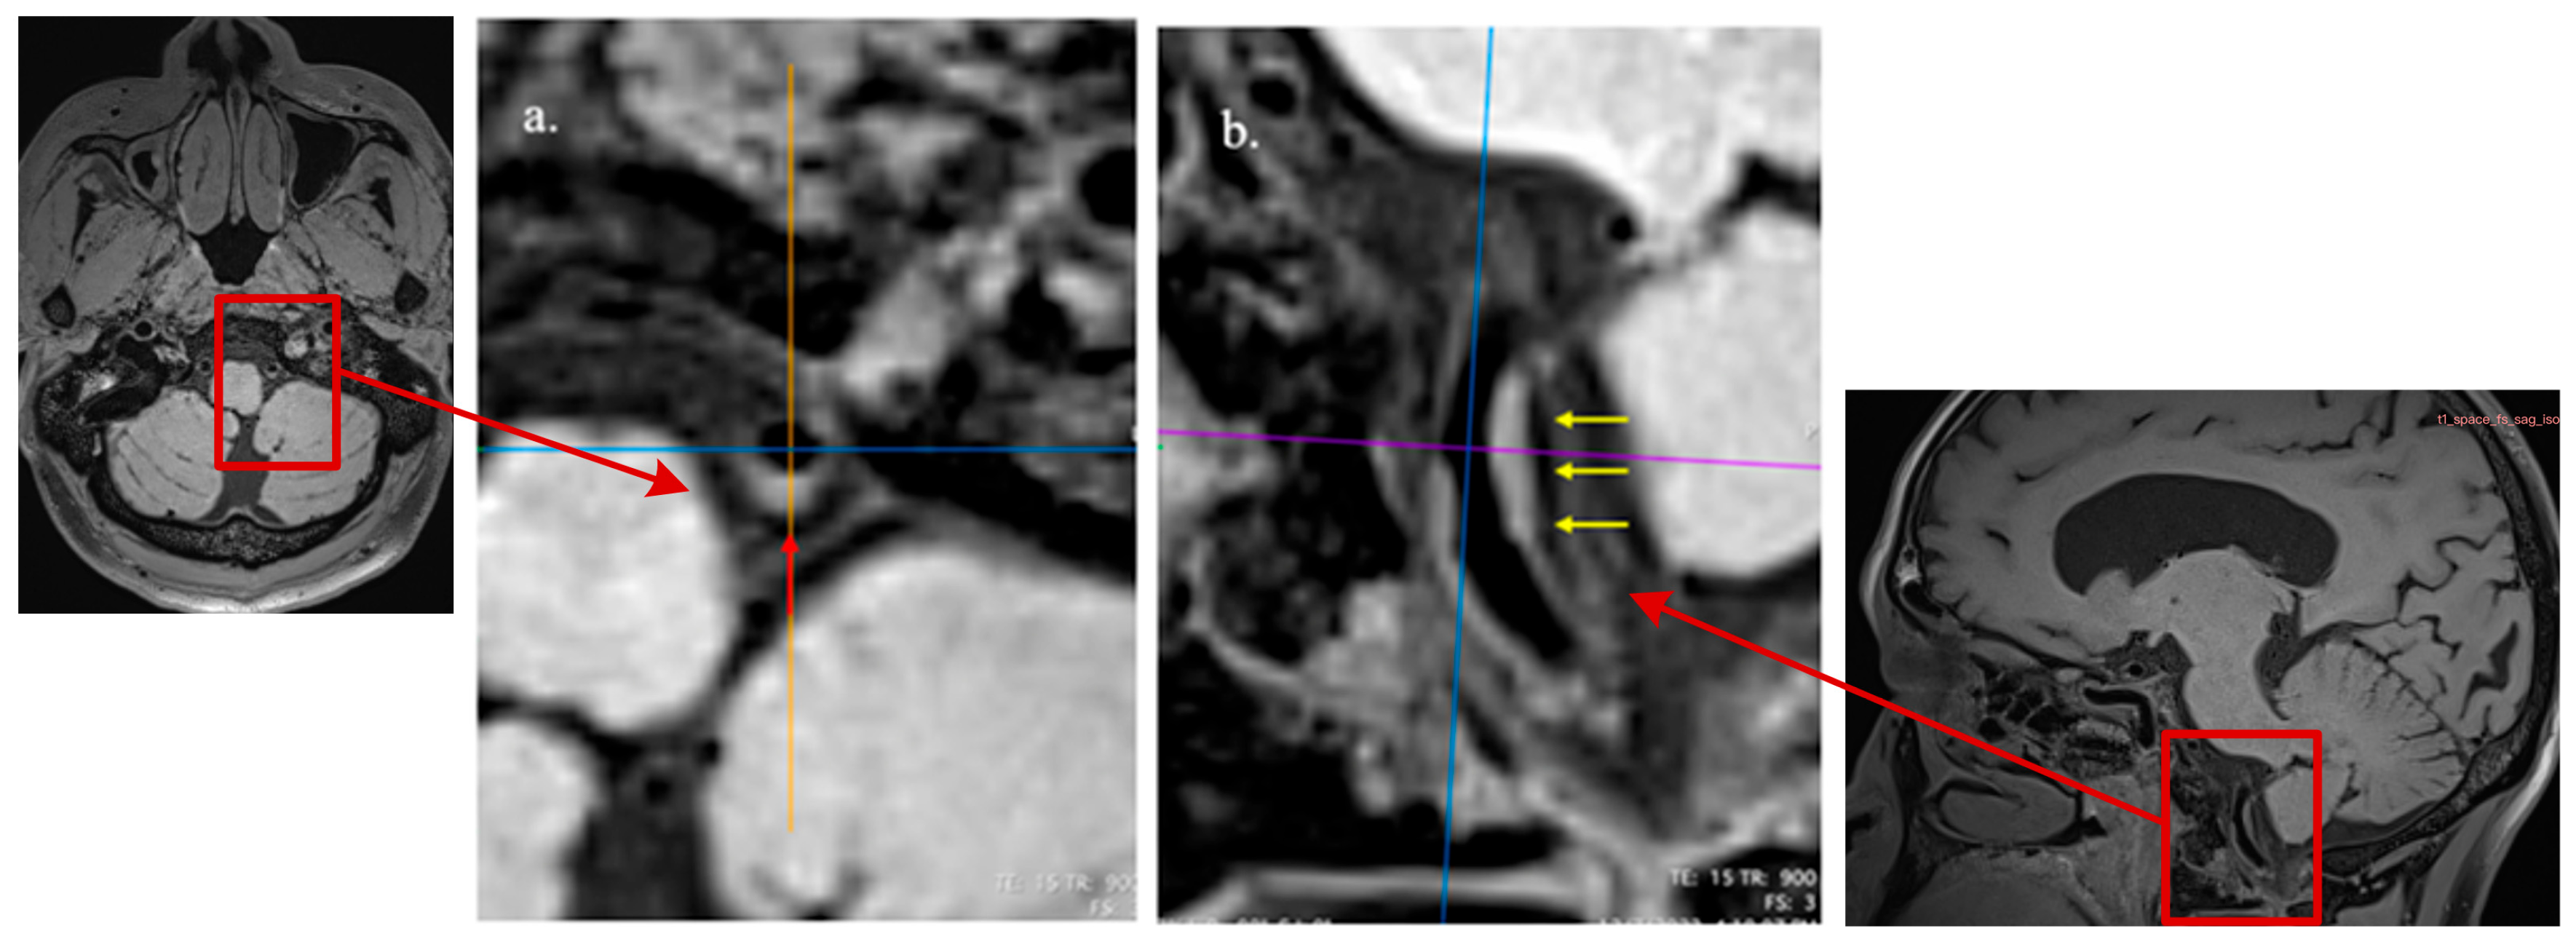

We analyzed all the plaques involving bilateral M1 segments of middle cerebral arteries (MCAs), the basilar artery (BA), and bilateral intracranial segments of vertebral arteries (VAs) by an intracranial artery illustration on the Circle of Willis (Figure 2) and longitudinal and cross-sectional HR-MRI imaging observations [31,32,33,34] (Figure 3). Based on the method described by previous studies [35,36], for each large artery, only the atherosclerotic lesion with the maximum wall thickness when two or more plaque lesions were identified was analyzed in this study using the nearest plaque-free cross-section proximal to the plaque as the reference site [31,37]. The assessment of the plaque imaging features included plaque burden [31], remodeling index (RI) [38,39], and other morphological patterns, e.g., focal/diffuse thickening patterns, irregular surface, and eccentricity [31,32]. We further assessed the degree of stenosis by a previously described method: (1-lumen area lesion/ lumen area reference) × 100% [31]. In light of the absence of well-defined criteria for precisely evaluating the severity of intracranial arterial stenosis and considering that major intracranial arteries are slightly narrower and have more branches than extracranial arteries, we followed previous reports in our classification. Vessels with stenotic degrees over 25% on HR-MRI were identified on the matched TOF-MRA and classified the stenosis as normal or <25%, 25–49%, ≥50% stenosis [40,41,42].

Figure 3. Diffuse and concentric pattern of plaque characteristics at cross-sectional and axial views. HR-VWI reveals mild stenosis of the left vertebral artery, as seen in the reconstructed cross-sectional view ((a), red arrow) and axial view ((b), yellow arrow).